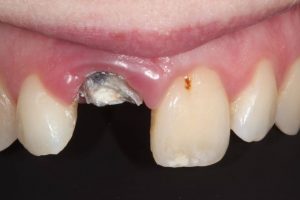

This patient had broken their upper front tooth and the exisitng dental crown had fallen off. The underlying root was unfortunatley irreparable.

The dental root was subsequently removed and an implant placed at the same time. The implant had a temporary crown placedon the same day.

The ‘After’ photos shows the final crown that was made after 3 months. The implant crown was made to match the form and colour of the exisiting teeth to give an overall natural aesthetic finish.